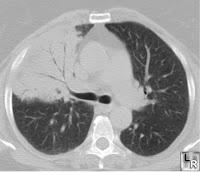

| Consolidated lung with air bronchograms |

This week we talked about the sensitivity and specificity of egophony in the diagnosis of pneumonia. Sensitivity can be defined as “positivity in disease,” and is expressed as the number of patients with a positive test result divided by the total number with the target disorder, giving the percentage of true positives in the diseased population. Specificity can be defined as "negativity in health," and is expressed the number of patients with a negative test result who don’t have the target disorder, giving the percentage of true negatives in the healthy population.

In our example, reference to the literature (McGee’s Evidence Based Physical Diagnosis,) suggested that the sensitivity of egophony for pneumonia is a paltry 4-16%, whereas the specificity is nearly 100%. So if you’re sure you hear it, you may not even need a chest x-ray to make the diagnosis – but the absence of this sign is basically meaningless.